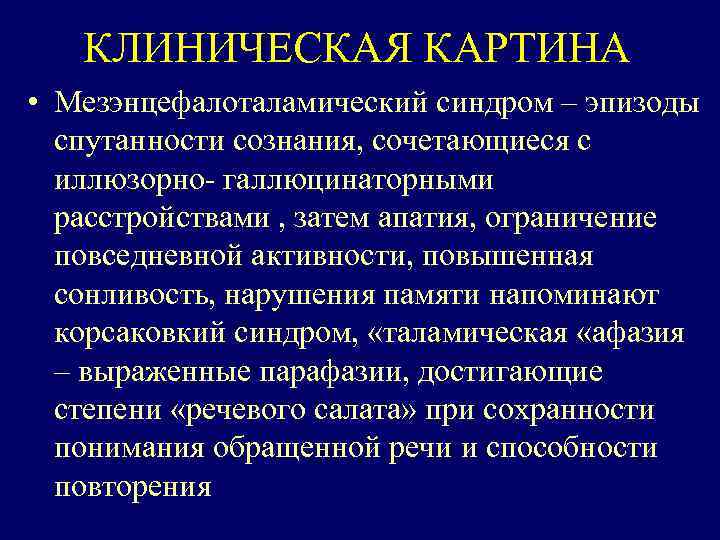

КЛИНИЧЕСКАЯ КАРТИНА • Мезэнцефалоталамический синдром – эпизоды спутанности сознания, сочетающиеся с иллюзорно- галлюцинаторными расстройствами , затем апатия, ограничение повседневной активности, повышенная сонливость, нарушения памяти напоминают корсаковкий синдром, «таламическая «афазия – выраженные парафазии, достигающие степени «речевого салата» при сохранности понимания обращенной речи и способности повторения